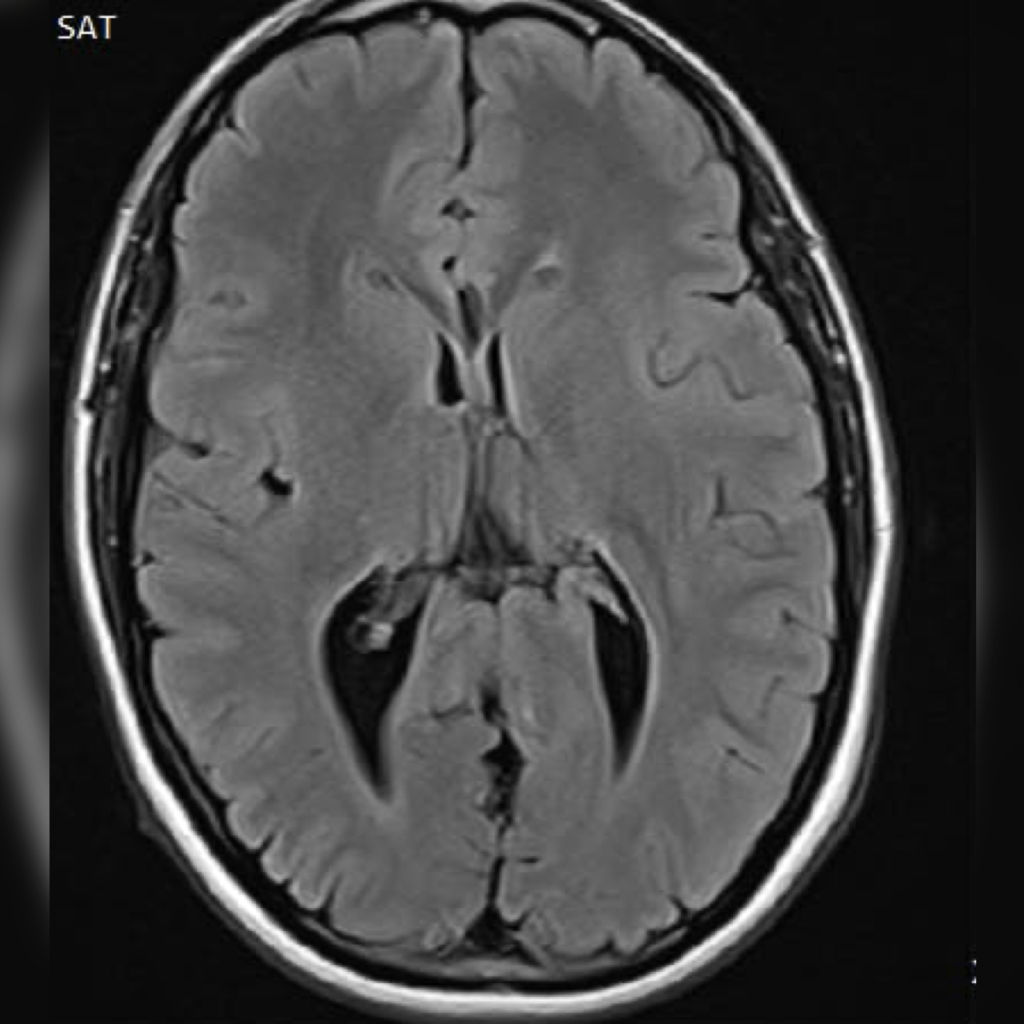

Neurology Patient Cases

Click on the image to see the full case details and sign in to view community comments.